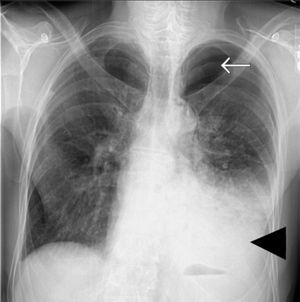

What's your dx? 1. Hydro-pneumothorax 2. Pericardial effusion 3. Lung necrosis 4. Emphysema